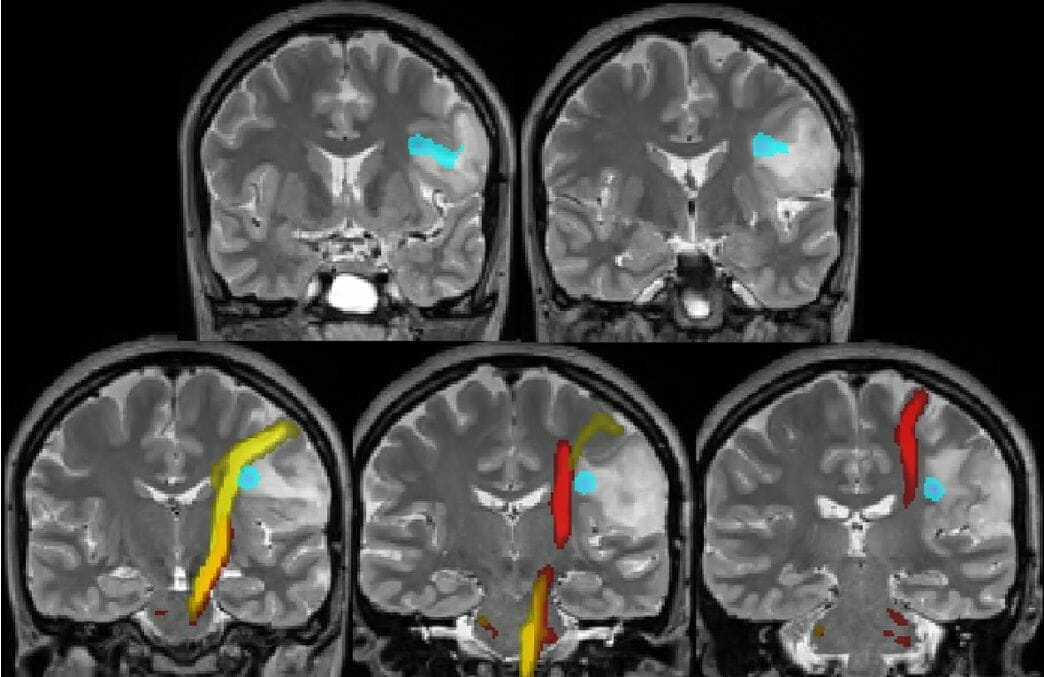

MR Guided Focused Ultrasound (MRgFUS) is an incisionless surgical treatment offering immediate, significant and durable improvement for Essential Tremor and Tremor-Dominant Parkinson’s Disease.